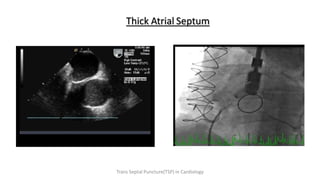

Thick Atrial Septum

Trans Septal Puncture(TSP) in Cardiology

Thick Atrial Septum TransSeptal Puncture(TSP) in Cardiology